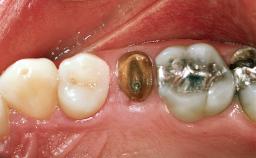

A healthy 26-year-old woman was referred for evaluation and treatment of her failing maxillary right central incisor (tooth 11). She reportedly traumatized the tooth at about age 9 and subsequently had repeated conventional and surgical endodontic procedures and fixed restorations. Despite these procedures, she had recurrent fistulas in the apical mucosa and a mid-facial pocket of 7 mm with suppuration. All other sites on the tooth probed 3 mm without inflammation. She presented with a medium biotype with triangularlyshaped teeth and a moderately high smile line, showing all of her papillas and a few millimeters of marginal gingiva in a full smile.Ceramic veneers were present on teeth 12, 21, and 22, and they were known to be somewhat bulky, eventually requiring replacement. She had a strong desire to avoid additional tooth preparation and would not consider a fixed dental prosthesis to replace tooth 11.

Shape of Tooth Crowns Rectangular Triangular

Soft Tissue Anatomy Intact Defective